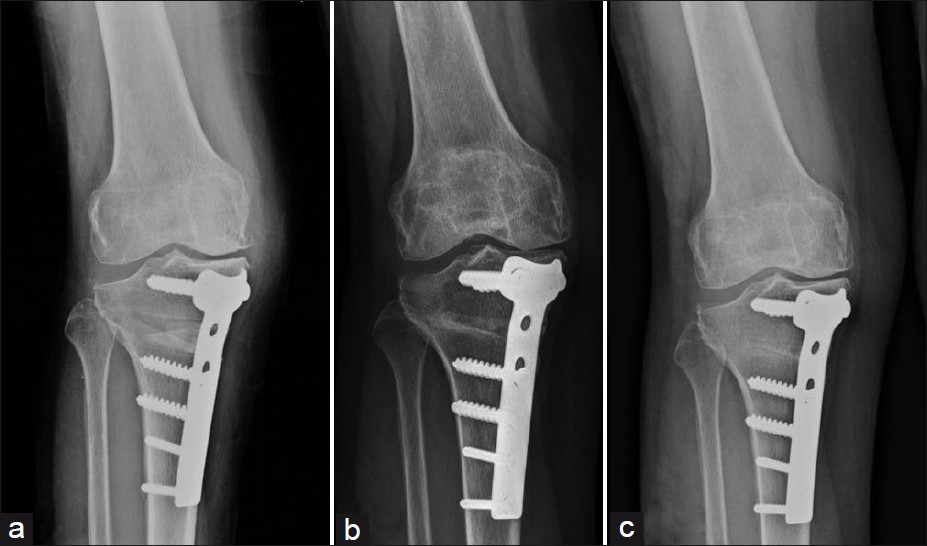

Surgeons perform High Tibial Osteotomy using advanced orthopedic surgical techniques.

Firstly, doctors conduct detailed clinical examination and imaging tests such as X-rays or MRI scans.

Secondly, surgical planning determines the exact bone correction angle.

During surgery, orthopedic surgeons make a controlled cut in the upper tibia bone.

After that, surgeons realign the bone structure to improve knee joint biomechanics.

Meanwhile, fixation plates and screws stabilize the corrected bone position.

Furthermore, modern surgical navigation tools help enhance accuracy.